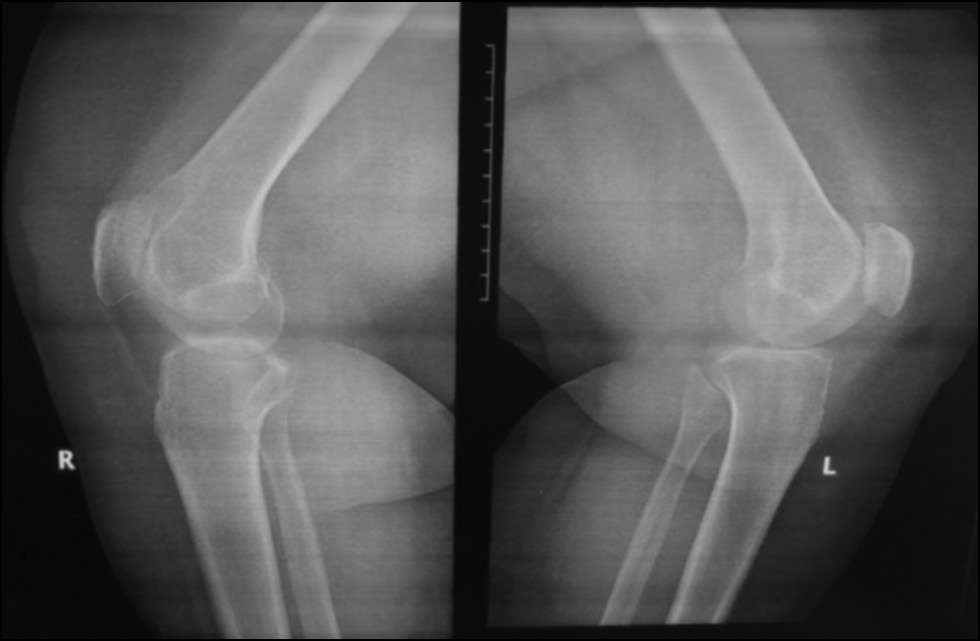

CASE 1. PATIENT 16

Age: 64 years.

Sex: Female.

Diagnosis: Bilateral advanced knee osteoarthritis.

Procedure: Bilateral simultaneous knee arthroplasty.

Associated illnesses: Hypertension.

Postoperative follow-up: No postoperative complications were encountered.

Length of hospital stay: 6 days.

Radiological assessment (Fig. 11–14)

Fig. 11. Ap preoperative x-ray showing bilateral knee osteoarthritis.

Рис. 11. Предоперационная рентгенограмма с двусторонним остеоартритом коленного сустава.

Fig. 12. Lateral preoperative x-ray right and left knees showing osteoarthritis.

Рис. 12. Предоперационная боковая рентгенограмма правого и левого колена с признаками остеоартрита.